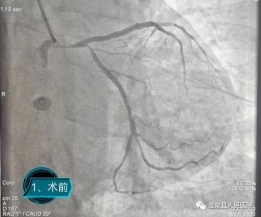

在咸宁市中心医院心血管内科李宾主任的指导帮扶下,温泉县人民医院介入诊疗中心团队开展心脏造影手术10台,其中PCI手术3台。并且成功开展我院首例冠状动脉左主干病变介入治疗,挽救了患者生命。冠状动脉左主干为整个心脏提供70%以上的血液供应,其急性闭塞意味着猝死的高风险,院外发病“九死一生”,又被称为“生命雷区”。此类手术在我院介入诊疗中心的顺利完成,标志着我院冠脉介入技术水平迈上新台阶,也将造福本区域更多的冠心病患者。